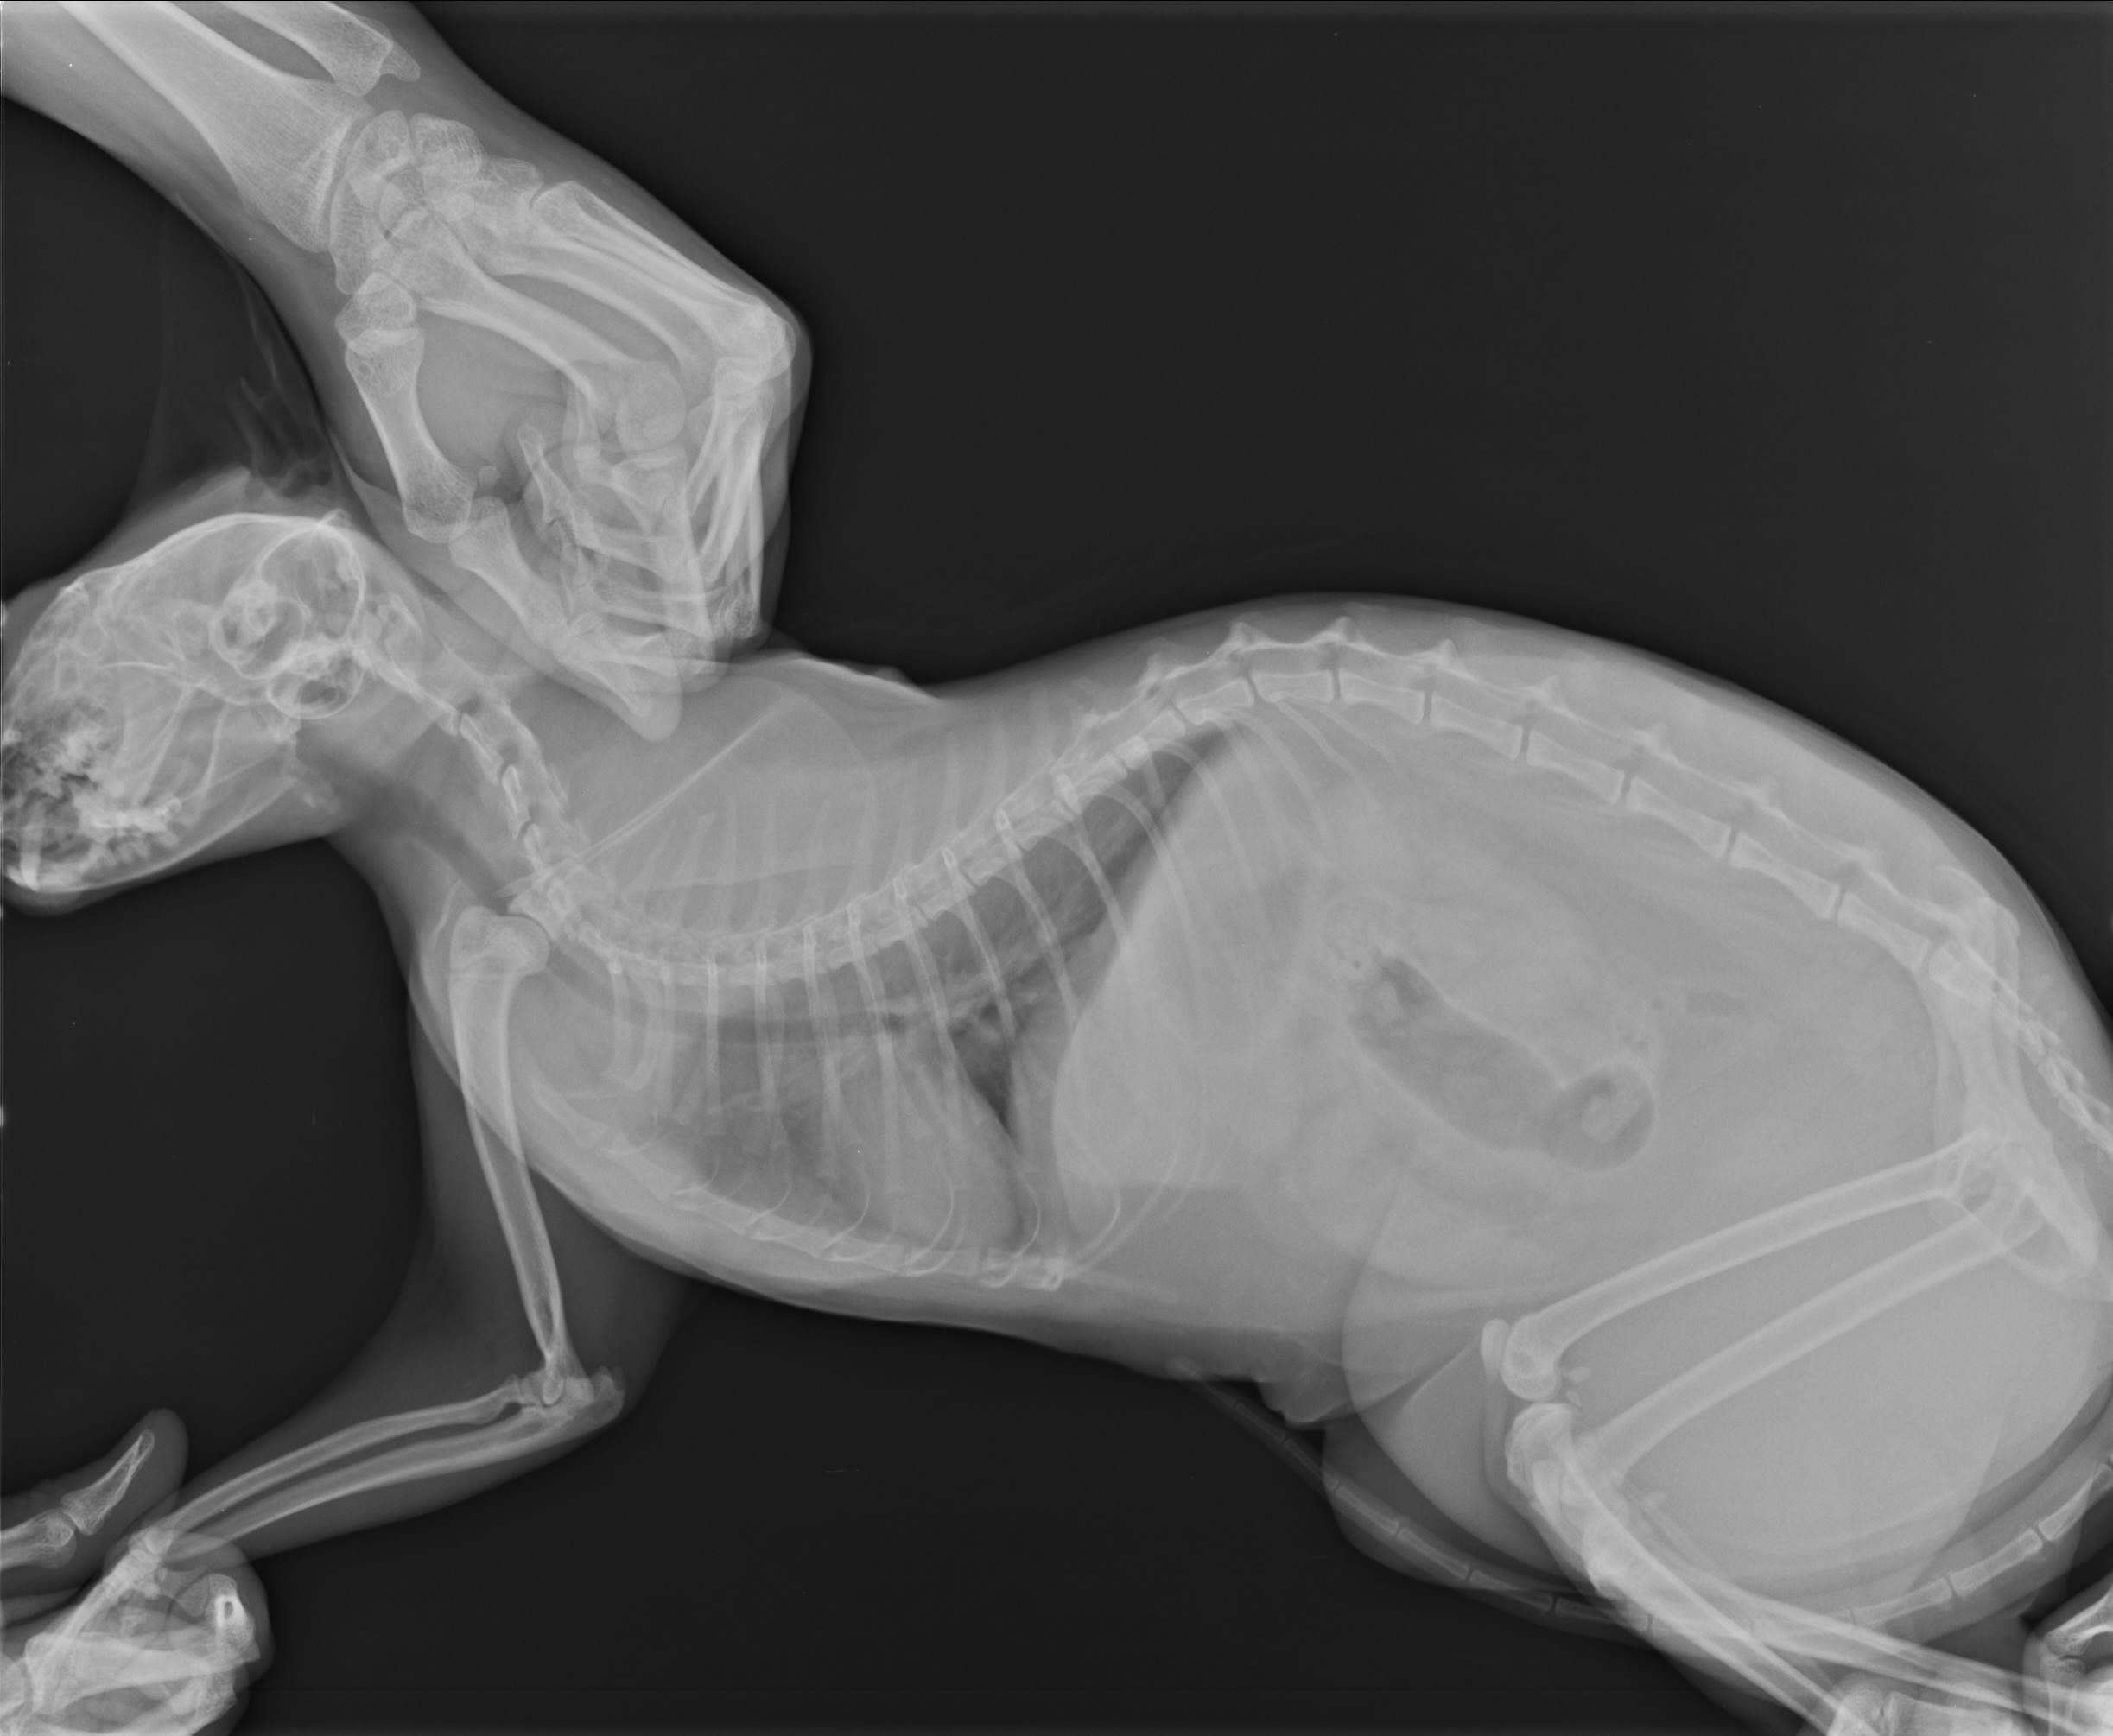

主題: 淚眼汪汪鼻塞無法呼吸的藍藍香 申請者姓名: 臺北市支持流浪貓絕育計劃協會 花色: 申請日期: 2013-11-20 18:09:57 申請者部落格: 申請者臉書網址: 所在縣市/合作醫院: 台北市/極光動物醫院 治療費用: 3510元 需求人數: 8人 已結案 (2014-01-10 17:49:31) 報名人員: Jeanine An(已付款)、Jason Chang(已付款)、ZLIN(已付款)、何偉靖(已付款)、蘇小吉(已付款)、grace(已付款)、Summer(已付款)、Sunny Chen(已付款)、 候補人員: 動物病情說明: 藍藍香在天氣轉換之際,開始出現鼻氣管炎的現象,補充離胺酸和營養品不見改善,狀況越來越惡化,看診醫師給予一些噴霧的藥劑和抗生素,第三天不見改善不吃不喝,再次就醫,一量居然發燒,仰頭張口呼吸,感覺很不舒服,怕有肺部感染的問題,拍X光檢查,所幸並沒有異樣,住院含噴霧、抗生素和打水退燒,三天後狀況穩定已帶回持續餵藥、噴霧治療。